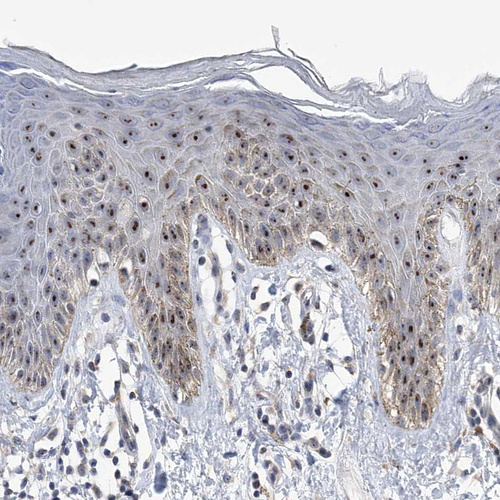

Immunohistochemical staining of human cerebral cortex, kidney, skin and testis using Anti-MPHOSPH10 antibody HPA035059 (A) shows similar protein distribution across tissues to independent antibody HPA035060 (B).